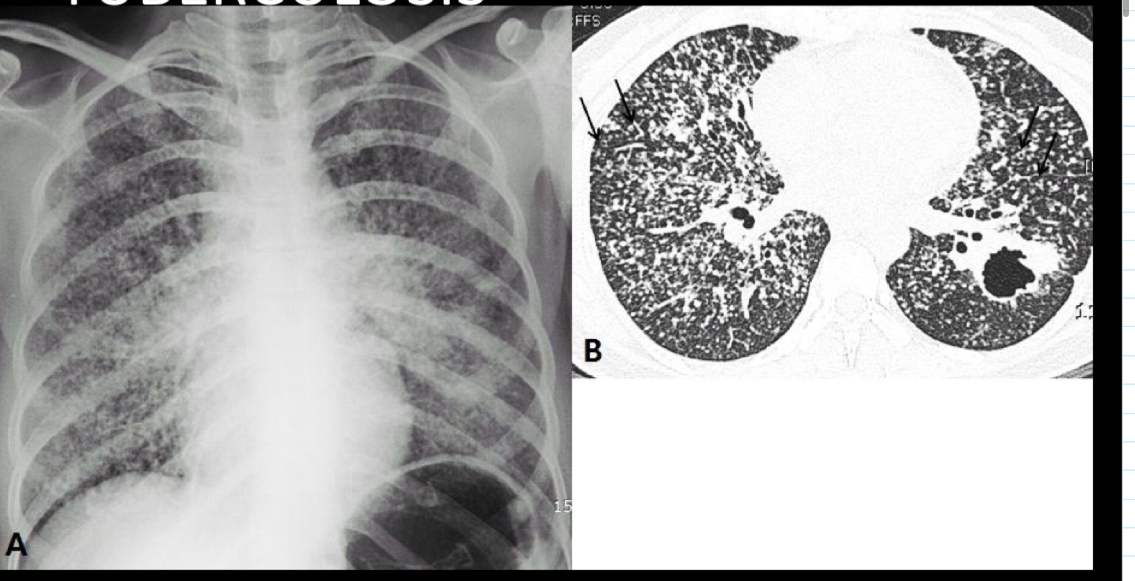

Que se ve en la miliar

muchos nódulos pequeños

Es rara y peor pronostico

Q piensas si ves árbol en brote o miliar

tb en inmunosuprimidos

Q es x vía hematogena

Puede ser febril o no